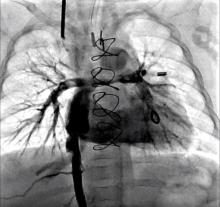

Results: The post-operative course was uneventful, and the patient was discharged on day 8. The follow-up exam at 5 months was satisfactory with angiographically-documented connection patency, and no veno-venous collaterals or hepatic vein congestion. The infant had oxygen saturations in the mid-80's, no ascites, and was feeding and gaining weight normally.